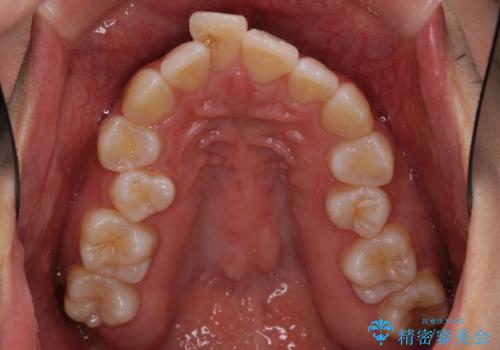

- 上下の歯の前後関係が乱れ、歯に負担がかかるとのことで来院された患者様です。

下顎が右左側に変位しているため、左側奥歯の咬み合わせが上下反対の関係となっていました。

また、上下ともに歯列が狭窄しており、奥歯以外にも反対咬合が認められました。

歯列全体の拡大と、歯と歯の間を削ることでスペースを獲得し、インビザラインによる矯正治療を行うこととしました。